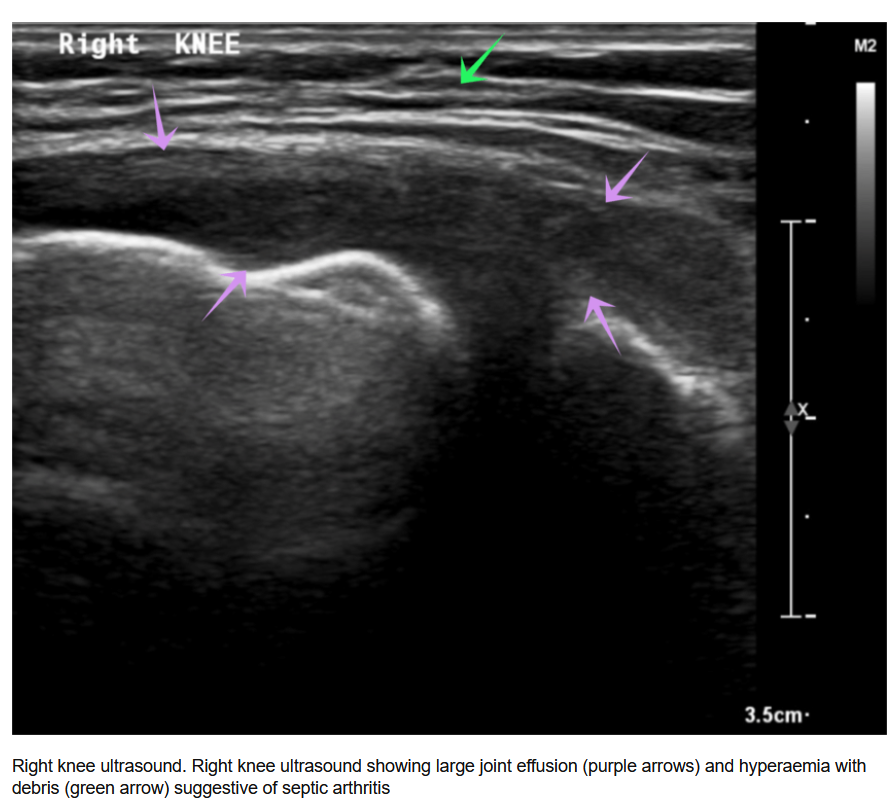

超声在检测和评估膝关节积液(液体积聚)方面有效,有助于诊断如骨关节炎和炎性关节炎等病症,并指导治疗抽液。